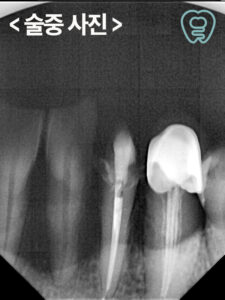

문제는 그뿐만 아니라, 남아있는 치아들도 뿌리만 남아있거나 염증으로 인해 예후가 좋지 않았는데요. 살려 쓸 수 있는 치아들은 신경치료와 크라운 수복을 통해 보존하도록 하고 불가피하게 발치가 필요한 치아들은 발치 후 즉시 임플란트 식립을 진행할 수 있도록 계획을 수립하였습니다.

먼저 위쪽의 치아들을 발치한 후, 당일 임플란트 식립을 진행하였고 이어서 아래쪽도 진행하였습니다.

인공치근과 잇몸뼈가 충분히 융합될 수 있는 기간을 기다려주는 동안 살려서 사용할 수 있는 자연치들은 신경치료 후 크라운 수복을 진행하였는데요.